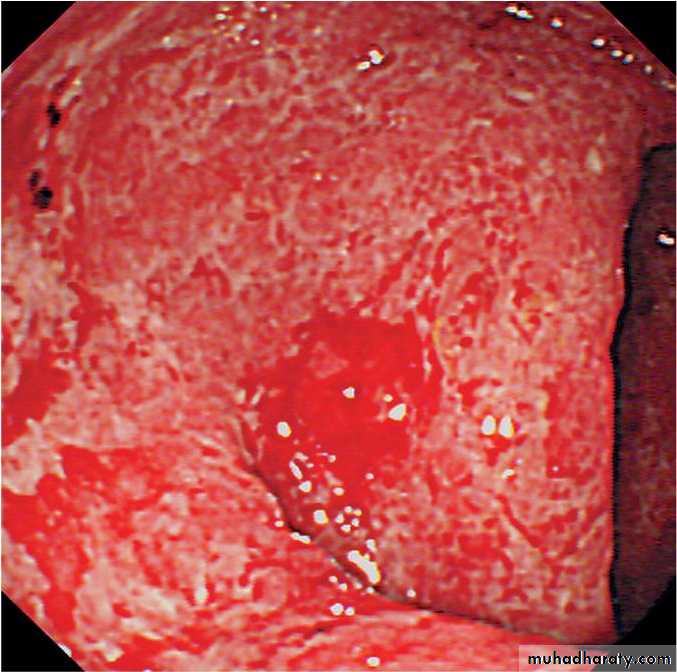

Sigmoidoscopy with biopsy is an essential investigation in all patients who present with diarrhoea, which show loss of vascular pattern, granularity, friability and ulceration

Sigmoidoscopic view of moderately active ulcerative colitis. Mucosa is erythematous and friable with contact bleeding. Submucosal blood vessels are no longer visible.